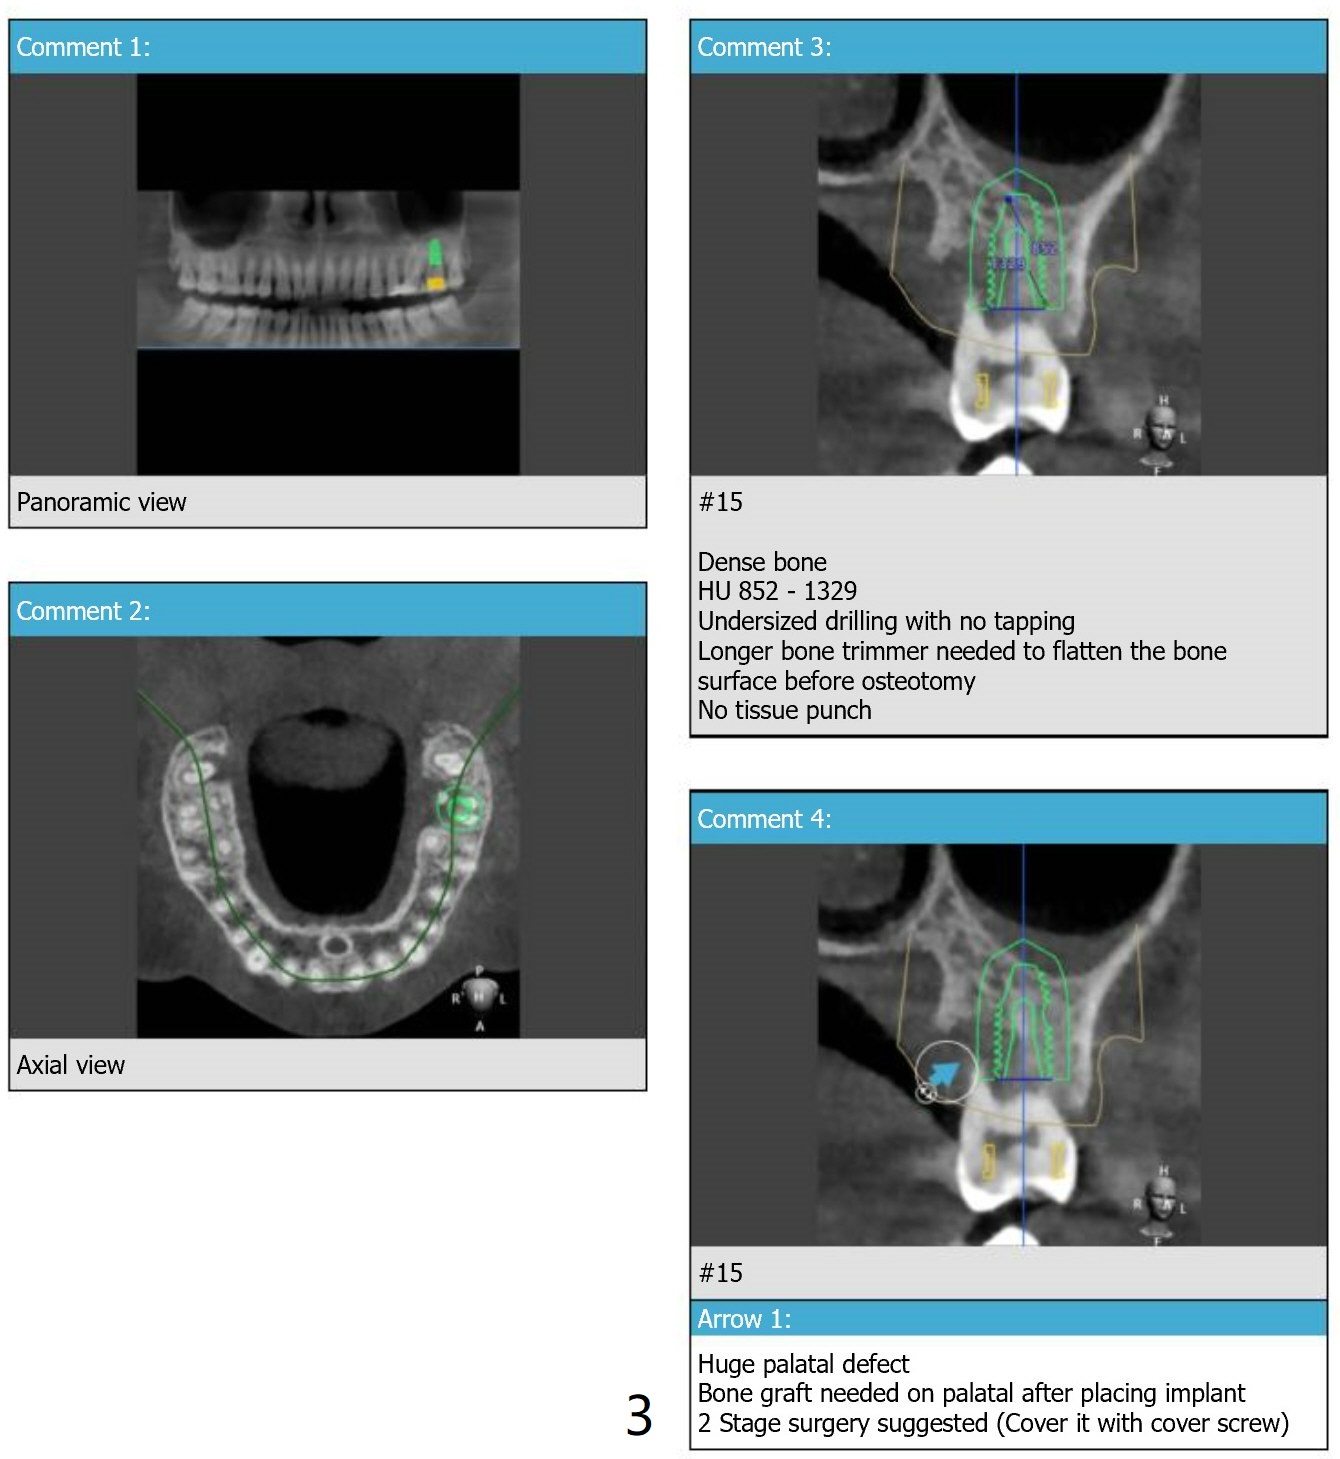

Prepare 2 tubes of PRF, one possible for sinus if the membrane happens to be perforated and the other to cover palatal bone graft. Also save autogenous bone.